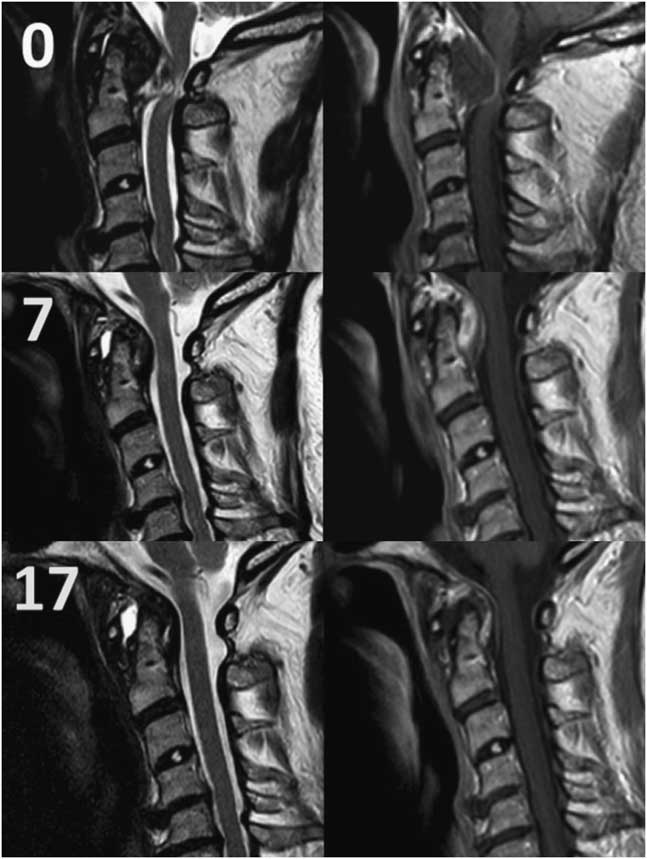

Cervical spine MRI revealed a retro-odontoid soft tissue mass, peripherally enhancing and mixed in signal intensity, measuring 1.5×2.2×1.2 cm (Figure 1). There was severe compression of the thecal sac at the level of the mass with local T2-hyperintense cord changes. Degenerative changes were present throughout the cervical spine. No atlanto-axial erosion was noted to suggest rheumatologic pannus or depositional arthropathy, nor was there surrounding bony destruction or enhancement to suggest malignancy. There was no widening of the atlanto-dental interval appreciated on these initial studies. These findings were corroborated with computed tomography for high-resolution bony visualisation.

Figure 1 Sagittal T2-weighted (left) and T1-post-Gadolinium contrast media (right) MRI of the cervical spine, at initial presentation, 7 months, and 17 months (from top to bottom).

She was seen in clinic 1 month post discharge and described significant improvement of neck pain and diminished myelopathic symptoms. In subsequent visits, fine motor function, walking distance, and gait continued to improve. She no longer required any gait aids. Repeat imaging at 7 months demonstrated significant lesion regression (Figure 1), as well as radiologic signs of AAI including increased pre-dental interval and mild subluxation (2.7 mm) on flexion-extension films. The patient reported compliance with the collar, although she found it uncomfortable and challenging. At 8 months, it was decided that the patient be weaned off the collar over the course of a month, with time off during the day while maintaining a soft collar at night. Moreover, she was instructed to be vigilant for symptoms of progressive myelopathy. At 17 months—9 months post weaning—her MRI did not show any recurrence (Figure 1).